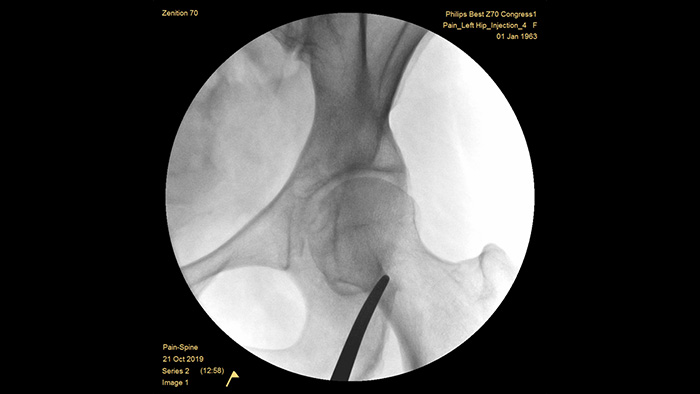

Mobile C-arms for pain management

Zenition 70 Mobile C-arm with Flat Detector

Enhance image quality and dose efficiency in complex and dense anatomy

With our fourth generation Flat Detector systems, you gain exceptional image clarity of dense and complex anatomy. The compact form provides ample space and positioning ease for treating chronic pain in the joints. Our Position Memory2 increases first-time-right positioning to reduce scout images3 for efficient workflow in pain management cases.

The Zenition 70 is available in two detector sizes: the FD 26 cm x 26 cm offers broad anatomical coverage, while the FD 21 cm x 21 cm provides ample space to work around patients.